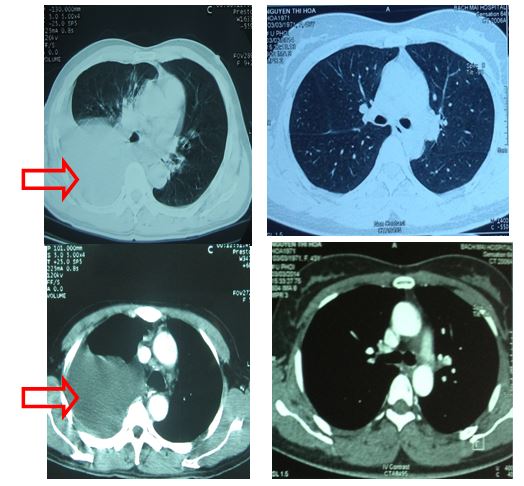

So sánh trước và sau điều trị:

Trước điều trị: ho, đau ngực phải, đau vùng cột sống lưng, đau vùng xương chậu phải, khó thở khi gắng sức

Sau điều trị: không ho, không đau ngực, không đau vùng lưng, hết đau vùng xương chậu phải, không khó thở

Trước điều trị: Tràn dịch màng phổi phải (mũi tên đỏ).                Sau điều trị: không thấy tràn dịch màng phổi phải

Sau 1 tháng điều trị: còn hạch rốn phổi phải,kích thước: 0,9 cm (vòng tròn vàng)

Sau 5 tháng điều trị: không còn hạch rốn phổi

Xạ hình xương trước điều trị: tăng hoạt độ phóng xạ (đầu mũi tên) tại đốt sống ngực 10 và khớp cùng chậu hai bên

Xạ hình xương sau điều trị: Tăng hoạt độ phóng xạ tại đốt sống ngực số 10, cung trước xương sườn 9,10; xương chậu bên trái (đầu mũi tên hình 11).

Hình ảnh tăng hoạt độ phóng xạ tại cung trước xương sườn 9,10 tương ứng với vị trí va đập trước khi làm xạ hình xương (vòng tròn vàng).